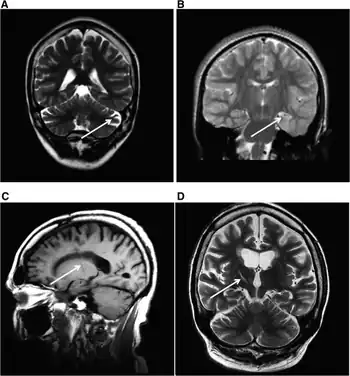

MRI (adult) showing cerebellar atrophy in Dravet syndrome

The cause if often a genetic mutation in the SCN1A gene.[4] Around 90% of mutations newly occur during early development, rather then being inherited from a person's parents.[3] A family history of seizures is present in nearly half of cases.[8] Diagnosis is based on symptoms and genetic testing.[5] MRI of the brain is typically normal initially, though may show changes such as atrophy in some adults.[2]

Brain MRI findings in adults with Dravet syndrome (and SCN1A mutation)